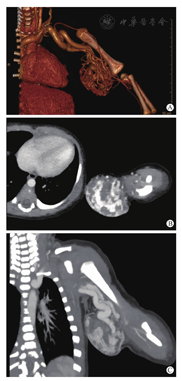

患儿男,44 h,因出生后发现左上肢包块,于2015年3月7日入院。患儿为第1胎第1产,孕39周+6,顺产,家族史无异常,孕晚期产检B超发现左上肢有一血流信号丰富包块。入院检查:左上臂近肘关节处可及一直径约5 cm包块,半球形隆起于皮面,皮肤表面呈淡蓝色,存在较多的血管扩张影,界清、质韧、无触痛反应,未及破溃和搏动感。辅助检查:当地医院查血常规示血小板(PLT)39×109/L[参考范围(100~300)×109/L]。入院后完善检查,血常规:WBC 4.77×109/L,HB 172 g/L,PLT 34×109/L。凝血常规:PT 17.0 s(参考范围10~14 s),APTT 49 s(参考范围25~45 s),Fbg 1.31 g/L(参考范围1.8~4.0 g/L),TT 20.1 s (参考范围12~21 s)。入院当天予血小板10 U输注,第2天复查PLT 327×109/L,行增强CT示左上臂明显强化的瘤体病灶,密度不均匀,CT值约31.4~51.5 HU,增强后包块内部可见多条异常迂曲血管影(图1)。诊断为RICH合并TP、CP。

最终我们这个病例诊断为RICH合并TP、CP,依据:①患儿孕期B超即已发现瘤体存在,瘤体的外观特征和之前广泛报道的RICH相类似[2],在随访过程中发现有明显的萎缩消退。②CT增强显示瘤体广泛地血管化(图1A),强化后密度不均匀(图1B),滋养血管粗大杂乱(图1C),这均与RICH的血管造影特征相符合[22]。③新生儿期内出现的TP、CP极为短暂、轻微且易于恢复,输注血小板后未见血小板报复性下降。④手术切除大体标本病理见大小不等小叶状结构,间质有明显的纤维增生,GLUT-1(-),D2-40(-),这是RICH较为特征性的病理表现[2,21],可以与KHE和VM/VLM相区别[11,12]。